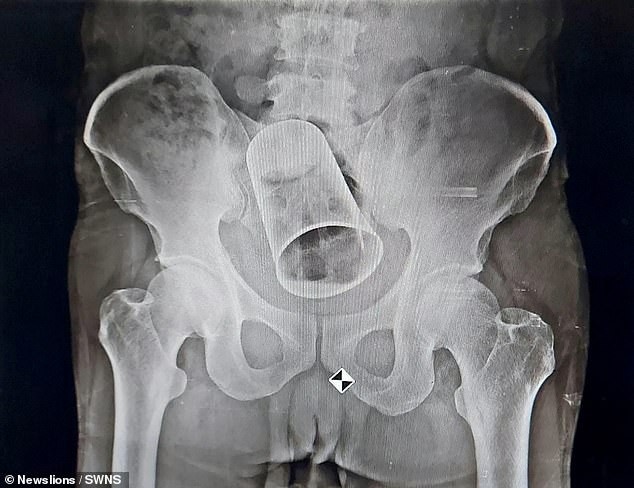

Mr Goatse begs to differ. But yeah that was my thought as well.Originally posted by Paddy View PostA physical impossibility and a dodgy looking x-ray. Must be fake.

Where has the p3n1s beaker gone darling?

Ah there it is..

Doctors remove a steel cup from a man’s rectum in India – TEN DAYS after ‘his friends inserted it as a drunken prank’

Got some great mates that fella.Tags: None